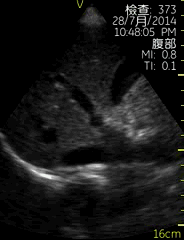

Vscan临床图片 腹部